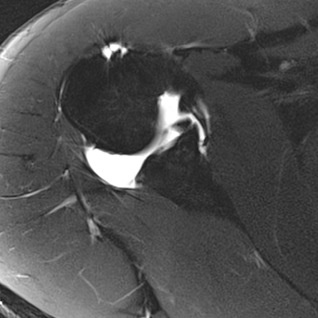

orthopaedie-zentrum-zuerich-mri-einriss-gelenkpfannenrand

MRI eines Einrisses des Gelenkpfannenrandes